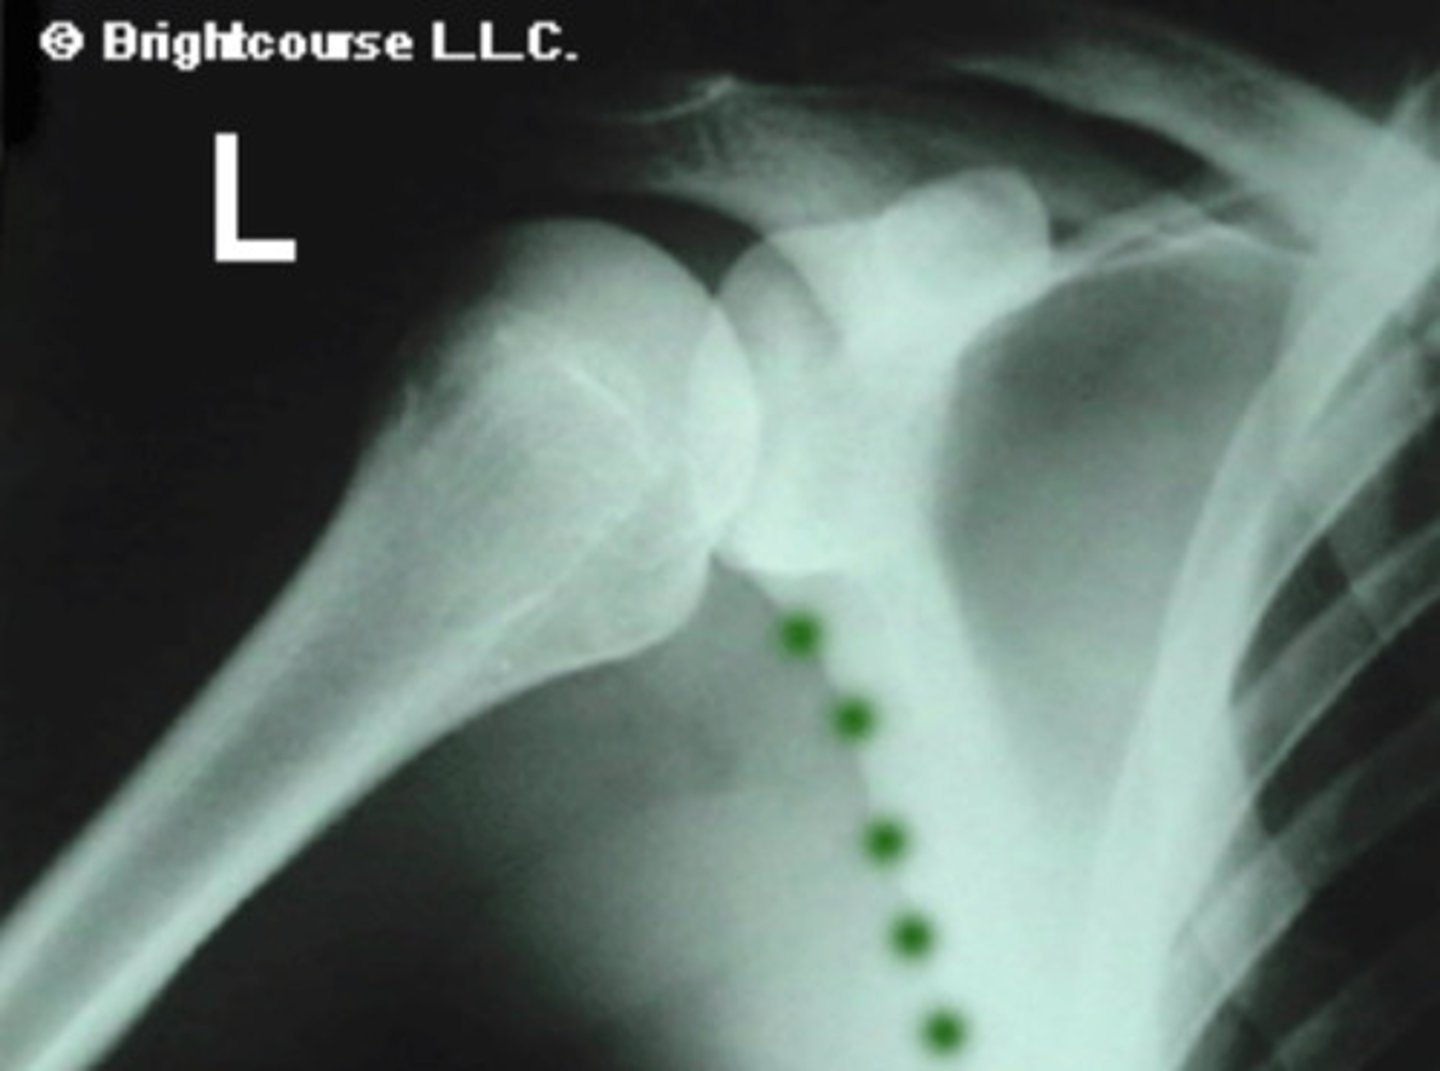

Anterior shoulder dislocation

What conditions would can an increases in the Acromiohumeral joint space?